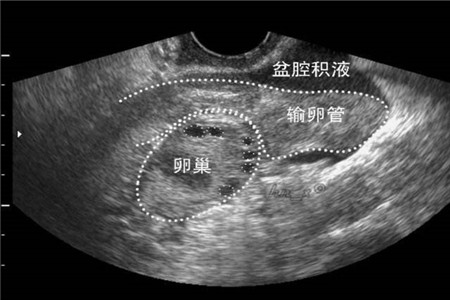

说到盆腔积液大家都知道,但并不了解。严格来说盆腔积液只是一种表现,但危害也是不容忽视的。那么你知道盆腔积液会不会影响到怀孕呢?平时又该怎么做才能治疗呢?不妨跟着小编一......